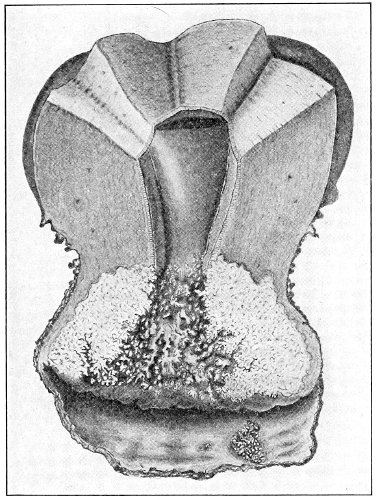

Papilloma.—Papillomata or warts of the vulva are not uncommon. They may occur singly, scattered over the vulva and the neighboring skin, and extending up the vagina as far as the cervix uteri, or they may occur in large cauliflower-like masses. They are pink or purplish in color. They often exude a bloody, offensive discharge, 47 which is capable of exciting a similar condition by contact. Papilloma is usually the result of gonorrhea or syphilis. It may, however, be caused by irritation from filth or by the leucorrhea of pregnancy.

The treatment of papilloma is by excision. The small warts should be picked up with forceps and clipped off with curved scissors. Every one should be removed or the condition may recur. In the case of large papillomatous tumors the wound of excision should be closed with continuous sutures. Pregnancy is no contraindication to excision of papillomata.